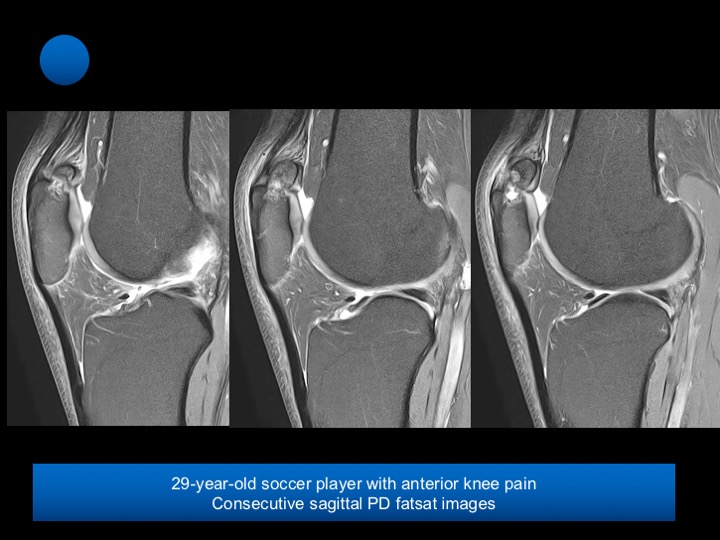

29-year-old soccer player with chronic anterior knee pain

Bipartite patella is a developmental variation in which peripheral, accessory ossification centers fail to fuse with the main body of the patella. While at least three different locations of bipartite patella have been described, it typically involves the superolateral aspect of the patella, at the insertion of the vastus lateralis muscle, is seen in approximately 2% of the population, and is almost always bilateral. Bipartite patella is more common in males tan females by a ratio of 9:1.

Bipartite patella is usually asymptomatic and is an incidental finding on radiographs. Only 2% become symptomatic and painful. The majority of painful bipartite patella are reported in young men who are actively involved in sporting activities.

Occasionally, in response to overuse or less common an acute injury, a synchondrosis may become either partly or completely disrupted, allowing abnormal motion, friction, and subsequently the development focal degenerative changes, and edema.

The most common presentation is with anterior knee pain on most activities involving extension of the knee. Reference article.